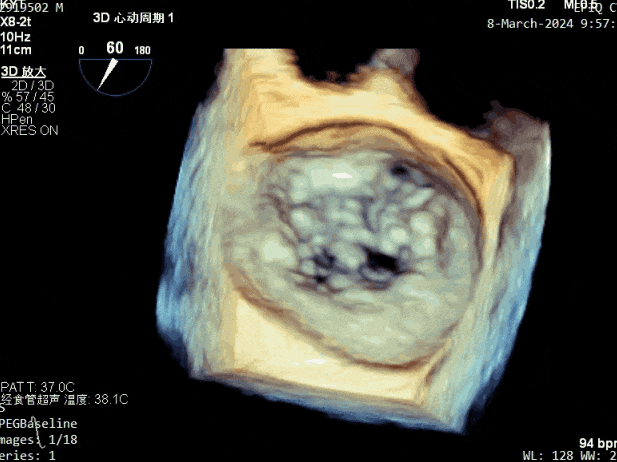

超声心动图:

二尖瓣后叶活动受限,呈房源性栓系,以P3区为重,二尖瓣前叶假性脱垂,二尖瓣瓣环前后径49mm,左右径40mm。

PISA法测r=12mm,EROA=0.72cm2,RVOL=100ml,RF 26%。LVEDD 57mm,左房71*59*77mm,右房55*69mm,LVEF 70%。

二尖瓣反流(重度,4+级,Carpentier I型)

2. 本例患者外院超声心动图考虑二尖瓣前叶脱垂,入院后经食道超声心动图明确该患者为二尖瓣后叶活动受限,呈房源性栓系,二尖瓣前叶假性脱垂,超声特征表现为心房功能性二尖瓣反流终末期,呈现出很典型的二尖瓣后瓣环向左室游离壁顶部位移和后叶挛缩表现,同时合并有明显的二尖瓣瓣环扩张、圆形化,左房增大等不利因素,术中通过精准的影像指导和手术操作,成功行TEER,二尖瓣反流程度减轻至微量。